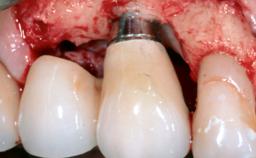

A 70-year-old female patient was referred by her general dentist to the periodontist for assessment and management of an infection associated with implant 36. The general dentist had noted suppuration on probing during examination.